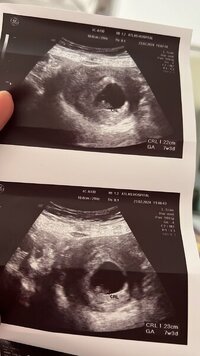

Selam banada bakarmısınız 7+3 karından

Ekli dosyalar

• 45a639a2-0c77-4877-8f07-fa6d62c7beef.jpeg

45a639a2-0c77-4877-8f07-fa6d62c7beef.jpeg

36,3 KB · Görüntüleme: 124